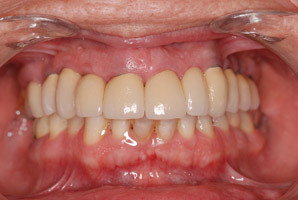

Aspect du bridge provisoire juste avant de confectionner le bridge d‘usage.

Aspect du bridge d’usage en zircone avant vissage.

Vue intraorale du bridge d‘usage en zircone avec contrôle du passage des brossettes. Les implants mandibulaires postérieurs sont prévus à court terme pour équilibrer l’occlusion.

Vue satisfaisante du sourire du patient.